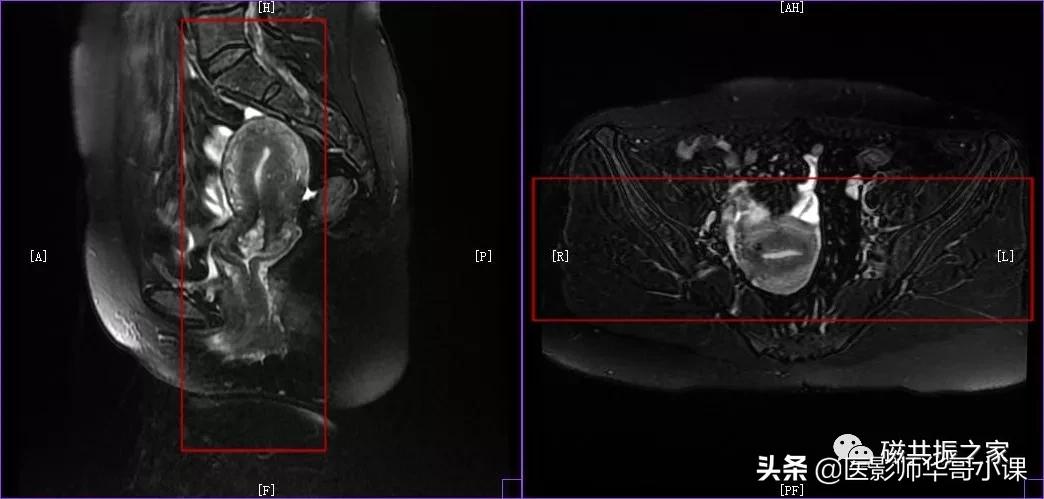

在横轴位和冠状位上定位。在横轴位上找到显示子宫体最大的层面,使定位线垂直于当前子宫内膜长轴,在冠状位上调整角度使定位线平行于子宫全长长轴(平行于子宫颈和子宫底中点的连线);如是宫颈病变,应以宫颈管为基准定位。左右扫描范围包括整个子宫,需包括整个病变范围。

矢状位是显示子宫全景较为理想的方位,该序列采用压脂或不压脂均可,但最好能做到小视野的高分辨率扫描。在T2WI上能清楚的显示子宫(绝经前)的四层结构。

子宫内膜:高信号

结合带:低信号

子宫肌层:中等信号

浆膜层:低信号